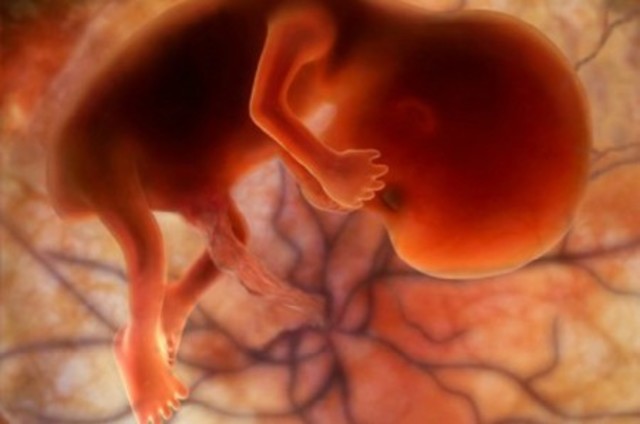

A partir de esta a semana se dice que comienza el periodo fetal. El feto ya tiene rodillas y sus miembros inferiores se flexionan sobre ellas. La placenta ya estará formada para esta semana. Los genitales continuarán su evolución dependiendo de los cromosomas sexuales. Durante esta semana, el feto crecerá 2 centímetros más.

• Semana 10

Semana 10

En esta semana se puede decir que la cara ya tiene aspecto humano porque la barbilla ya crece en proporción. Las orejas todavía están implantadas levemente bajas. Los genitales adquieren características femeninas o masculinas, sin embargo aun no están completamente formados. Al final de esta semana, el feto mide aproximadamente 6 centímentros.